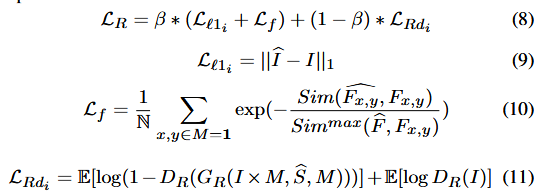

3.1.2 精炼模块

在 PTM 之后,由于监督信息被过滤以平滑高频信息,因此需要另一个精炼生成器

G

R

G_R

GR 和相应的判别器

D

R

D_R

DR 来在 RM 中生成更逼真的图像。

整个精炼过程可以表示为:

其中

I

I

I 是最终生成的图像,损失函数可表示为:

其中,

L

l

1

L_{l1}

Ll1 是精细重构损失。借鉴 [35] 的思想,

L

f

L_f

Lf 使用 Appearance Flow,用于比较输入图像中缺失区域

F

x

,

y

^

\hat{F_{x,y}}

Fx,y^ 的特征与 Ground Truth 特征

F

x

,

y

F_{x,y}

Fx,y 之间的余弦相似度(Sim(·))。N 是集合 M = 1 中的元素数量。

L

R

d

L_{Rd}

LRd 是判别器

D

R

D_R

DR 的对抗损失。

β

\beta

β 用于调整各损失之间的权重。